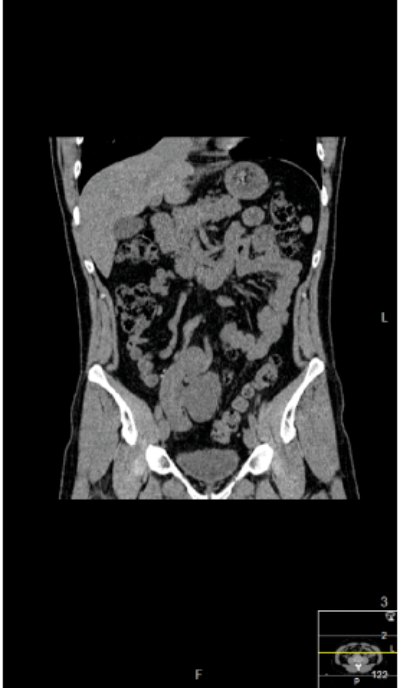

Preoperative IVU and CT demonstrating very little overlying renal cortex in duplex system.

Seven years postoperatively. New left staghorn calculus and right-sided fragment demonstrated outside the kidney.